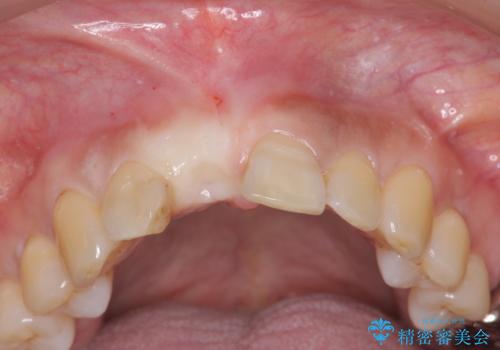

- 目立つ一番前の歯を失い、接着剤で応急処置をしていましたが永続性のある修復を希望され来院されました。

入れ歯・ブリッジ・インプラントによる欠損補綴の方法のうち審美的で取り外しがなく隣の歯を削らない治療を望まれたため、インプラントによる審美・機能回復治療を計画します。